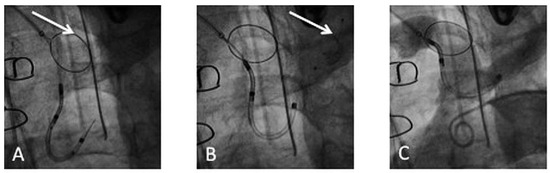

An 83-year-old man with ischaemic heart disease and a triple bypass in 2007 presented to the emergency department with increasing shortness of breath and weight gain of 5 kg over one month [...]